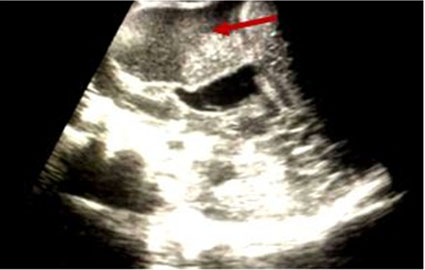

Contrast cranial CT scan done showed right deep frontoparietal cerebral abscess aborting on the falx cerebri and extending across the midline, associated with effacement of ipsilateral lateral ventricles and midline shift (see Figure 1). The abscess cavity was approached via the shortest trajectory while avoiding eloquent areas identified anatomically.

Figure 1: Contrast cranial computed tomography showing a frontoparietal intraparenchymal abscess (red arrow).

Figure 2: Parasagittal ultrasound image showing an echo-rich thick walled abscess cavity located at the frontoparietal region (red arrow) with associated compression of the ipsilateral lateral ventricle.